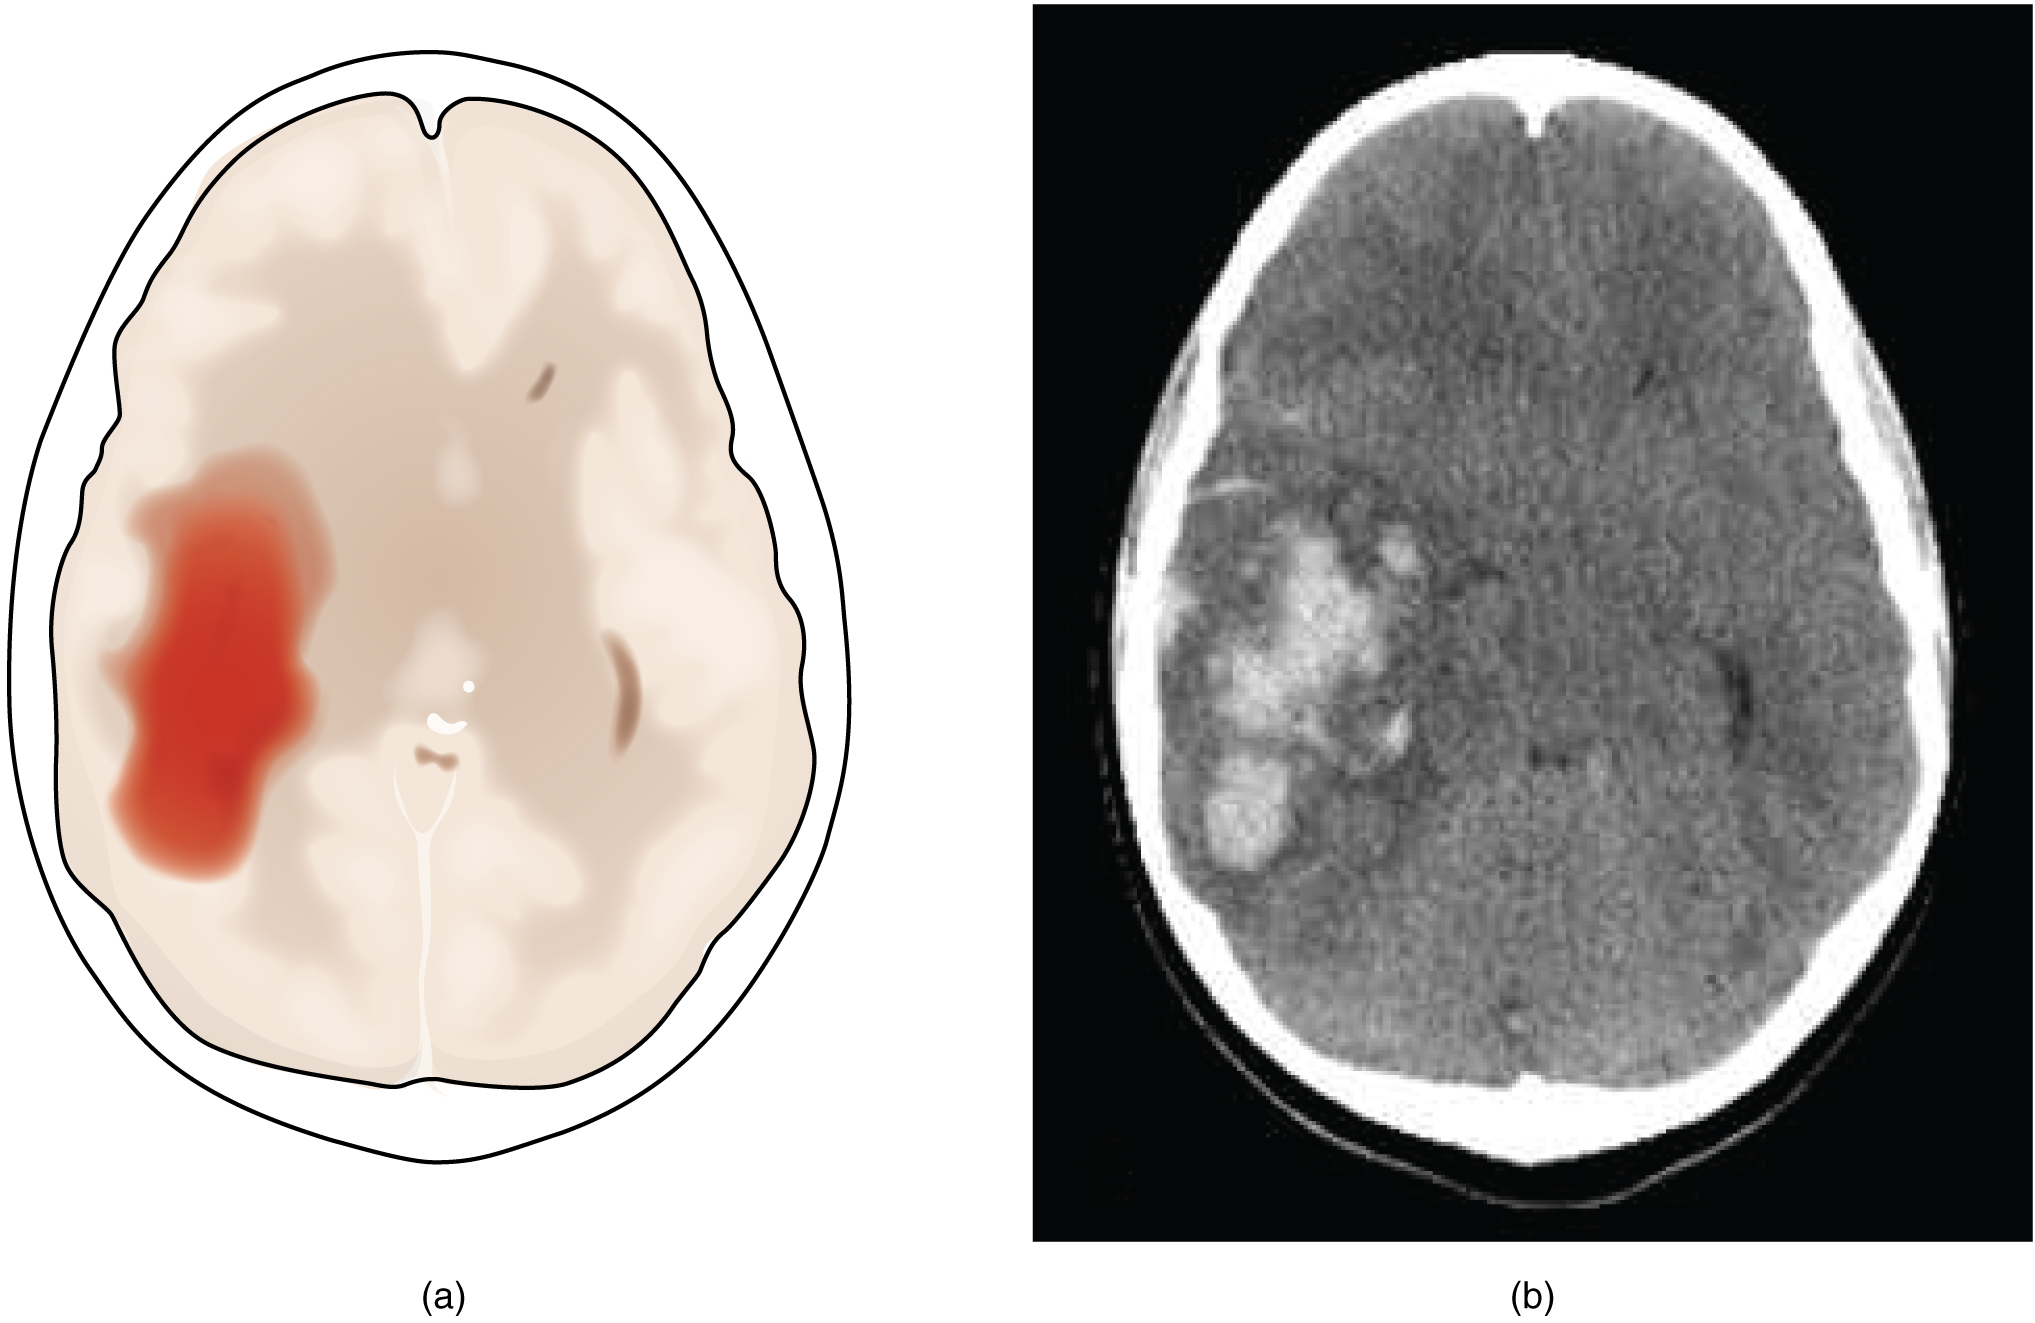

Инсульт. Источник: Anatomy & Physiology, Connexions Web site